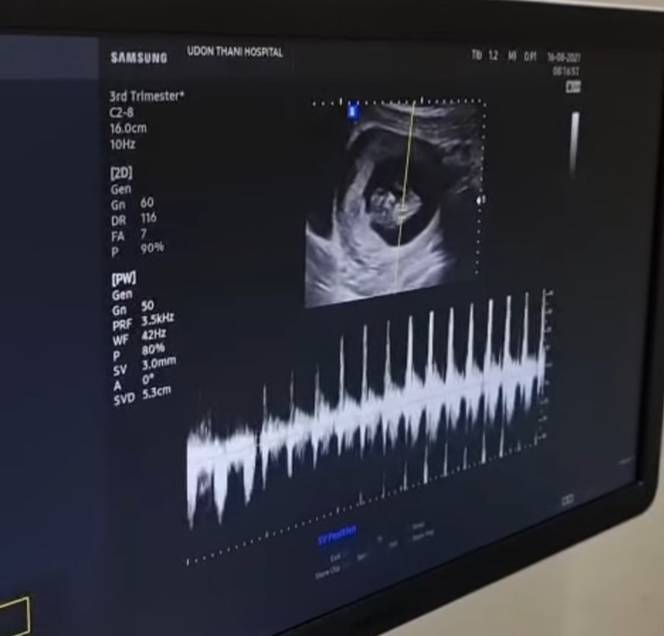

ล่าสุดนักแสดงสาวได้โพสต์อินสตาแกรมส่วนตัว เป็นภาพที่เจ้าตัวกำลังทำการอัลตร้าซาวด์ทายาทน้อยในครรภ์ พร้อมประกาศข่าวดีว่าตอนนี้ตั้งครรภ์ได้ 10 สัปดาห์แล้ว โดยระบุแคปชั่นว่า “หัวใจเจ้าจิ๋วเต้นดังสุดๆ ต้องใจใหญ่เหมือนหม่ามี้แน่เล๊ย555555 #เข้าสู่วงการหม่ามื้มือใหม่ #สถานีต่อไปลุ้นเพศ #10weekspregnant”